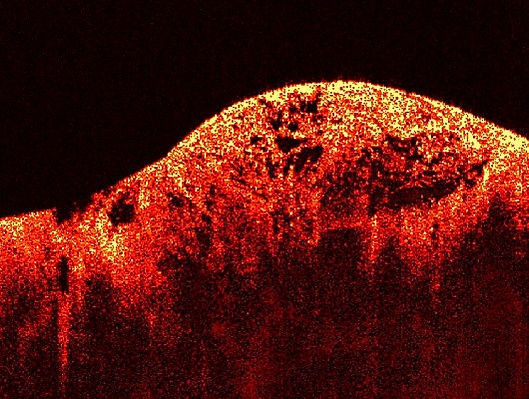

| Изображение саркомы сделано с помощью оптической когерентной томографии (ОКТ) | |